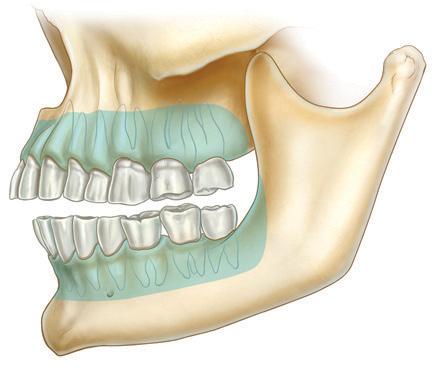

Orthognathic surgery, a discipline dating back to the 1840s, addresses maxillomandibular disharmonies and enhances both aesthetic appearance and function.1 This surgical field has had substantial advancements from its inception, particularly following the contributions of Hugo Obwegeser, who introduced techniques such as the bilateral sagittal split and Le Fort I osteotomy, which remain integral to contemporary orthognathic surgery.2 In recent years, advancements in the accuracy of computed tomography (CT) and cone beam computed tomography (CBCT) have spurred a shift towards three-dimensional (3D) virtual surgical planning (VSP).3 The widespread use of VSP has led to evidence supporting its accuracy in orthognathic surgery planning and execution.4

The adoption of VSP has revealed a plethora of advantages. Notably, Swennen and colleagues underscored the potential of VSP planning in assessing treatment outcomes through voxel-based rigid registration and superimposition techniques.3 Additionally, VSP serves as a communication tool among specialists, technicians and patients, with applications in education.3 VSP offers benefits such as enhanced accuracy in condylar positioning through splint construction using computer-aided design and computer-aided manufacturing (CAD and CAM), improved diagnosis and quantification of facial asymmetry, and potentially increased cost-effectiveness.5

In all cases that involved the maxilla, a Le Fort I osteotomy was conducted. In cases that involved the mandible, a bilateral sagittal split osteotomy was performed. Standard fixation miniplates and screws were used in all cases. If both mandible and maxilla movements were required, then the Le Fort I osteotomy was completed and fixated with miniplates before the mandibular movements.